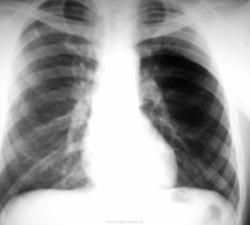

А, что за тень на 2 ребре справа?

Похоже на нечто плотненькое. Хотя, на мой взгляд, справа есть и другие тоже неоднозначные тени.

Поланда синдром (Poland syndrome)

Синдром Поланда (СП) представляет собой комплекс пороков, включающий отсутствие большой и малой грудной мышц, синдактилию, брахидактилию, ателию (отсутствие соска молочной железы) и/или амастию (отсутствие самой молочной железы), деформацию или отсутствие нескольких ребер, отсутствие волос в подмышечной впадине и снижение толщины подкожно-жирового слоя. Отдельные компоненты этого синдрома впервые были описаны Lallemand LM (1826) и Frorier R (1839). Однако назван он по имени английского студента-медика Alfred Poland, который в 1841 году опубликовал частичное описание данной деформации. Полную характеристику синдрома в литературе впервые опубликовал Thompson J в 1895 году.